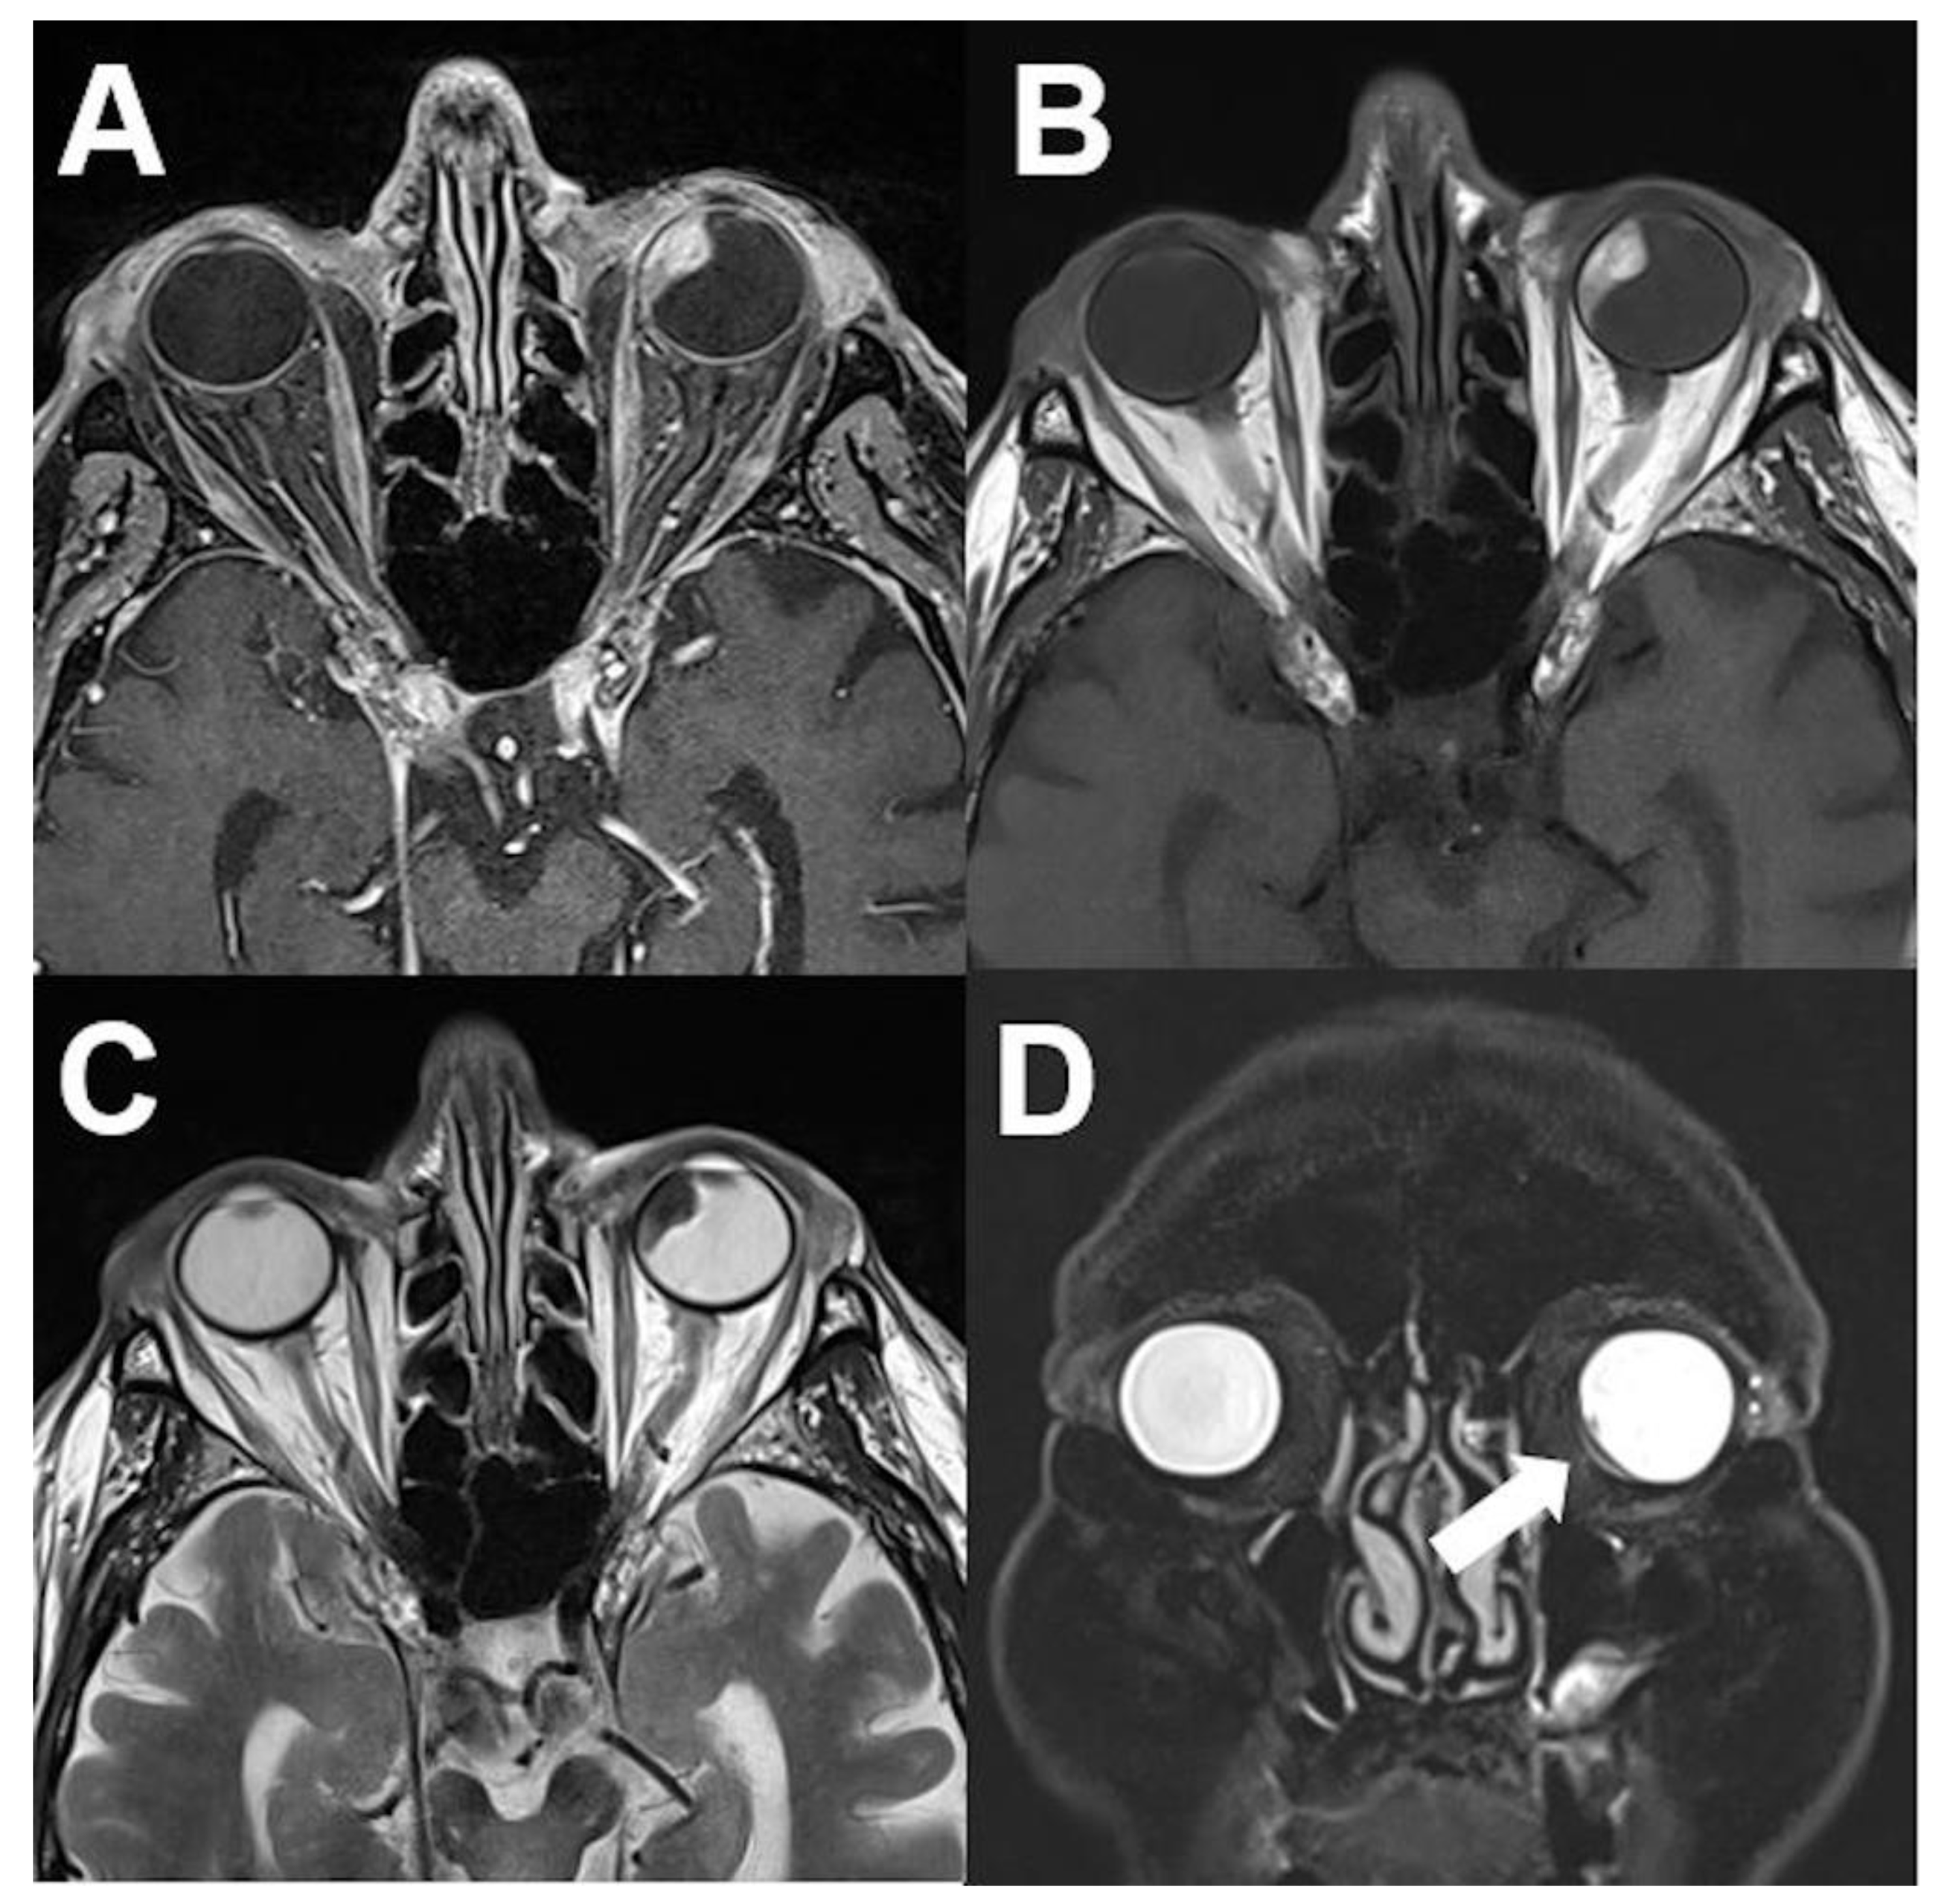

3.1. Intraocular Tumors

3.1.1. Retinoblastoma

3.1.2. Uveal Melanoma